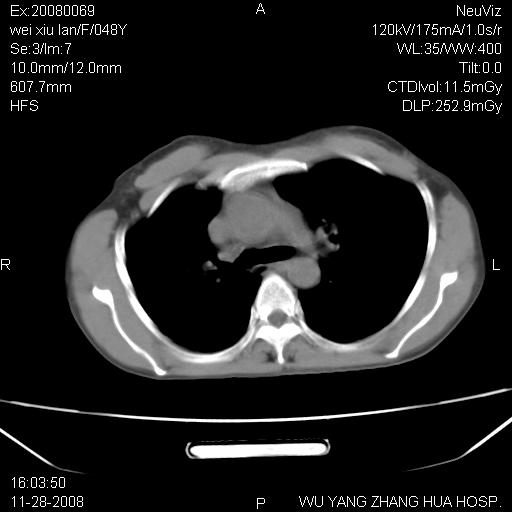

标题: CT16847:女,48岁,咳嗽,发热两日,平常偶有上腹部不适。 [打印本页]

标题: CT16847:女,48岁,咳嗽,发热两日,平常偶有上腹部不适。

能否考虑食管裂孔疝?请老师们多多指教。

这个是左侧膈膨升伴不完全性胃翻转,手术将松弛的左横膈膜折叠缝合即解决问题。

支持左侧膈疝,心脏受压右移.

左下肺不张、膈膨升,胸腔胃

胃、脾脏及部分肠管明显升高,并压迫心脏移位,

首先考虑:左侧膈疝。

左侧胸腔内见胃肠及脾脏影

支持膈疝